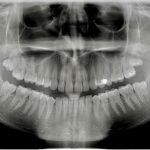

• Ortopantomogram (panoramska snimka): Cjelovit prikaz čeljusti i zuba, potreban za prvi pregled, vađenje zuba kod oralnog kirurga, za ortodonciju i čitav niz ostalih stanja i bolesti zubi i usne šupljine te se smatra najčešćom snimkom digitalne zubne dijagnostike. Ortopan snimka u svakodnevnoj praksi među doktorima dentalne medicine je sinonim za ZUBNI RENDGEN

Primjer jednog ortopana